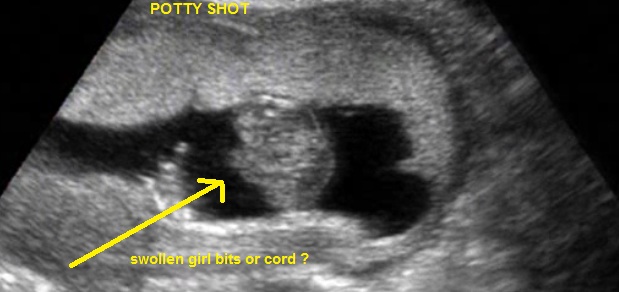

Your second and third shots are cord shots. I did not once see something that made me say 100% yes or no. They did very good trying to hide the gender. Every time it would just about come into focus, they would move baby so you wouldn't see anything. The cord was in between the legs 80% of the video. The other times when you see three lines around the bum thats a combo between cord and foot. Don't take false hope because several times I could have said girl or boy, but these two make me wonder. With 3d ultrasound at this gestation gender cant accurately be determined because its not high quality enough. These two shots are what put doubt in my head.Attachment 23024 Attachment 23025

sooooo i have spamed this forum with my pics, sorry, but today i watched the videoi i slow motion and got these shots, they are not screaming girl or boy, it is so crazy??? 3d is really bad for gender as nahri says .....but i tried it again...